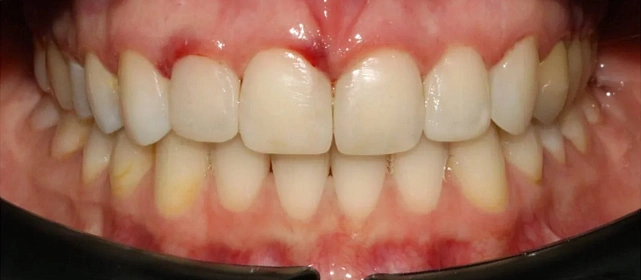

Обратилась с жалобой на скученность верхней и нижней челюсти средней степени тяжести — рецидив после подросткового лечения (ретейнер не носила).

КЛКТ, интраоральное сканирование, пародонтологическое обследование. Подвижности зубов нет, глубина зондирования — в пределах нормы.

Убыль кости — начальная, не превышает 1/4 длины корня.

рецессия десны в области нижних резцов, старые композитные пломбы на боковых зубах.

полное выравнивание зубных рядов без удаления зубов. Рецессия десны не прогрессировала (контроль по КТ через 12 месяцев). Пациентка носит несъёмные ретейнеры

и ночные капы.